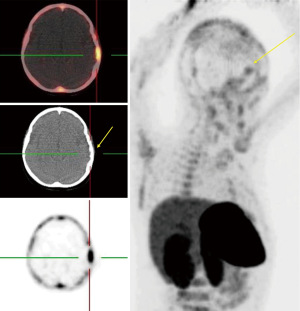

Assessment of response to treatment using hybrid imaging

Regarding the highly aggressive and heterogeneous nature of brain tumors, especially GBM as the most common and fatal of those, earlier response assessment is vital in the management of brain tumors. At present, current clinical practice relies upon conventional imaging to appraise the response. It remains a challenge to determine the treatment efficacy due to the lack of accuracy of conventional modalities in differentiating between pseudoprogression (PsP) including treatment-induced changes, and true tumor progression (tumor growth or recurrence) (6,11). In recent years, investigators have made great efforts to overcome the challenges through utilizing molecular imaging like PET imaging, which uses a vast range of tracers with different properties, and with combined anatomical and functional modalities e.g., PET/MR (11,29-32). FDG-PET, the current standard PET agent, utilization in differentiating between pseudo- and true progression has shown variable results (6). In addition, high background uptake may limit its ability regarding small lesion detection (11). Recently, new PET tracers have demonstrated better results than the traditional FDG-PET in differentiating PsP and true progression of tumors (33,34). Gao et al. evaluated the diagnostic precision of 11C-choline PET in differentiating PsP from true tumor progression through a meta-analysis. With a total of 118 patients (134 scans), the pooled sensitivity and specificity were 0.87 (95% CI: 0.78, 0.93) and 0.820 (95% CI: 0.69, 0.91), respectively. They conclude that 11C-choline has the potential to differentiate PsP and true progression of tumors (35). Some studies have further suggested that O-[2-(18F)fluoroethyl]-L-tyrosine (18FET)-PET can potentially solve this problem (31,36). Galldiks and colleague studied the detection of pseudoprogression in glioblastoma patients using 18F-FET-PET. They investigated a total of 22 patients with new contrast-enhanced (CE) areas or lesions that enhanced with contrast (>25%) on MR imaging during the first 12 weeks after finishing the course of therapy. Patients underwent 18F-FET-PET as well to differentiate PsP from true progression. They showed that the best 18F-FET TBRmax cut-off value for diagnosis of PsP was 2.3 (sensitivity 100%, specificity 91%, accuracy 96%) (31). Lohmann et al. explored the potential of combined FET-PET/MRI in distinguishing of PsP from true progression in the brain metastasis. A total of 52 patients who showed new or progressive contrast-enhancement lesions on MR imaging after ending the radiotherapy underwent the FET-PET as well. The results showed that the CE-MRI had an accuracy of 81% (sensitivity, 67%; specificity, 90%) in PsP diagnosis. The diagnosis accuracy for FET-PET was 83% (sensitivity, 88%; specificity, 75%). They combined the two modalities and achieved a diagnostic accuracy of 89% (sensitivity, 85%; specificity, 96%). Thus, it may be the right time to shift from conventional imaging to the fused anatomical/molecular imaging approach which uses new agents to improve diagnostic accuracy and provides further insight into the tumor characteristics (Figure 3).